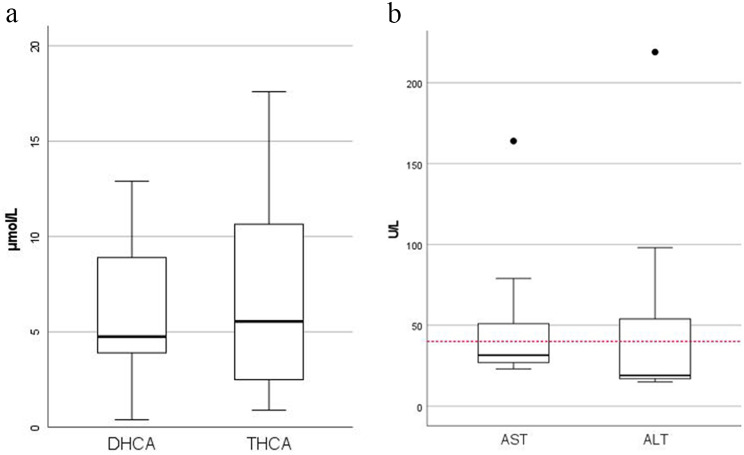

Bile acid intermediates (R)-DHCA and (R)-THCA were elevated in all patients. The median DHCA level in plasma was 4.8 µmol/L (reference value 0.0 µmol/L) and THCA level in plasma was 5.6 µmol/L (reference value 0.0–0.1 µmol/L) (Fig. 5a). In one patient the primary bile acid cholic acid in plasma was below the lower limit of normal (reference value 0.1–4.7 µmol/L) and in five patients the primary bile acid chenodeoxycholic acid was below the lower limit of normal (reference value 0.7–10.0 µmol/L). In four patients, urinary bile acids were measured and C27-bile acid intermediates in urine were detectable in two of those patients. Pristanic acid was elevated in all patients (median 77.0 µmol/L, reference value 0.0–1.6 µmol/L). Phytanic acid was normal in six patients (median 9.5 µmol/L, reference value 0.49–9.88 µmol/L), but it was unclear whether some of these patients were already on a phytanic acid-restricted diet at the time of analysis.

Blood samples obtained after diagnosis, prior to possible vitamin supplementation, were analyzed for liver function tests, fat soluble vitamins and coagulation parameters. No coagulation parameters and vitamin levels were available for patient 1. Patient 3 was excluded from analysis of liver function tests because of liver cancer at the time of diagnosis. All 11 other patients had normal (total) bilirubin and alkaline phosphatase levels at the time of diagnosis. Only one adult had a slight elevated gamma-glutamyl transferase level in plasma. Five patients had elevated aspartate aminotransferase (AST) levels (median 51 U/L, range 46–146), three of whom are children. All three children also had elevated alanine aminotransferase (ALT) levels (54, 98 and 219 U/L respectively), which none of the adults had (Fig. 5b).